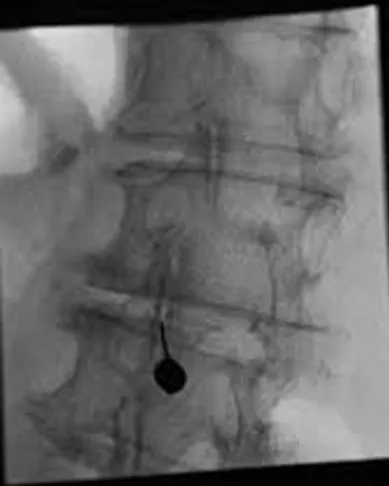

Decided to proceed with Right sided L5 and S1 Transforaminal Epidural Steroid Injections

Transforaminal Epidural Steroid Injection

First Lumbar Bilateral L5-S1 Transforaminal Epidural Steroid Injection 11/01/2016 > 30% Relief

Second Lumbar Bilateral L5-S1 Transforaminal Epidural Steroid Injection 11/29/2016 > 50% Relief

Third Lumbar Bilateral L5-S1 Transforaminal Epidural Steroid Injection 12/27/2016 > 70% Relie